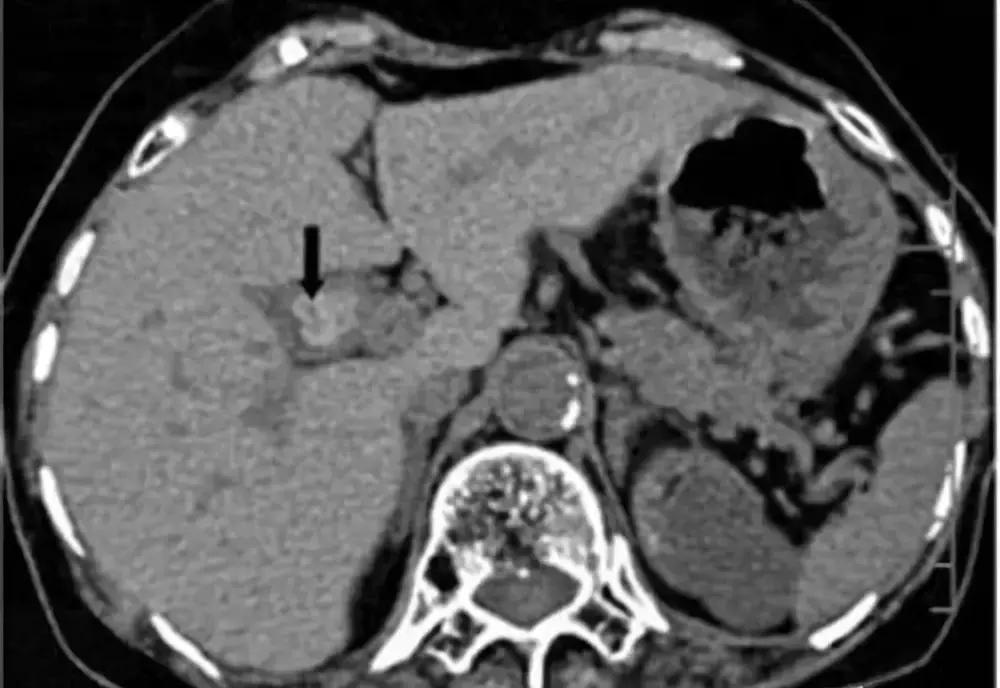

胆囊息肉是胆囊壁向腔内呈息肉样突起的一类病变的总称,包括肿瘤性息肉和非肿瘤性息肉,一般症状轻微,甚至无症状。

目前胆囊息肉的病因尚不清楚,长期饮酒,高脂饮食,不吃早餐、压力大、熬夜及生活不规律者,容易得胆囊息肉。胆囊息肉以良性息肉更为多见,但也要预防癌变。

一旦发现就要定期复查,如果符合以下手术指征,建议尽早手术治疗。如胆囊单发息肉直径超过1厘米以上,蒂粗大者,尤其是基底宽,位于胆囊颈部,年龄超过50岁;胆囊多发息肉合并胆囊结石且有症状;胆囊息肉直径小于5毫米,无症状,要每3~6个月随访,迅速增大或症状明显等。